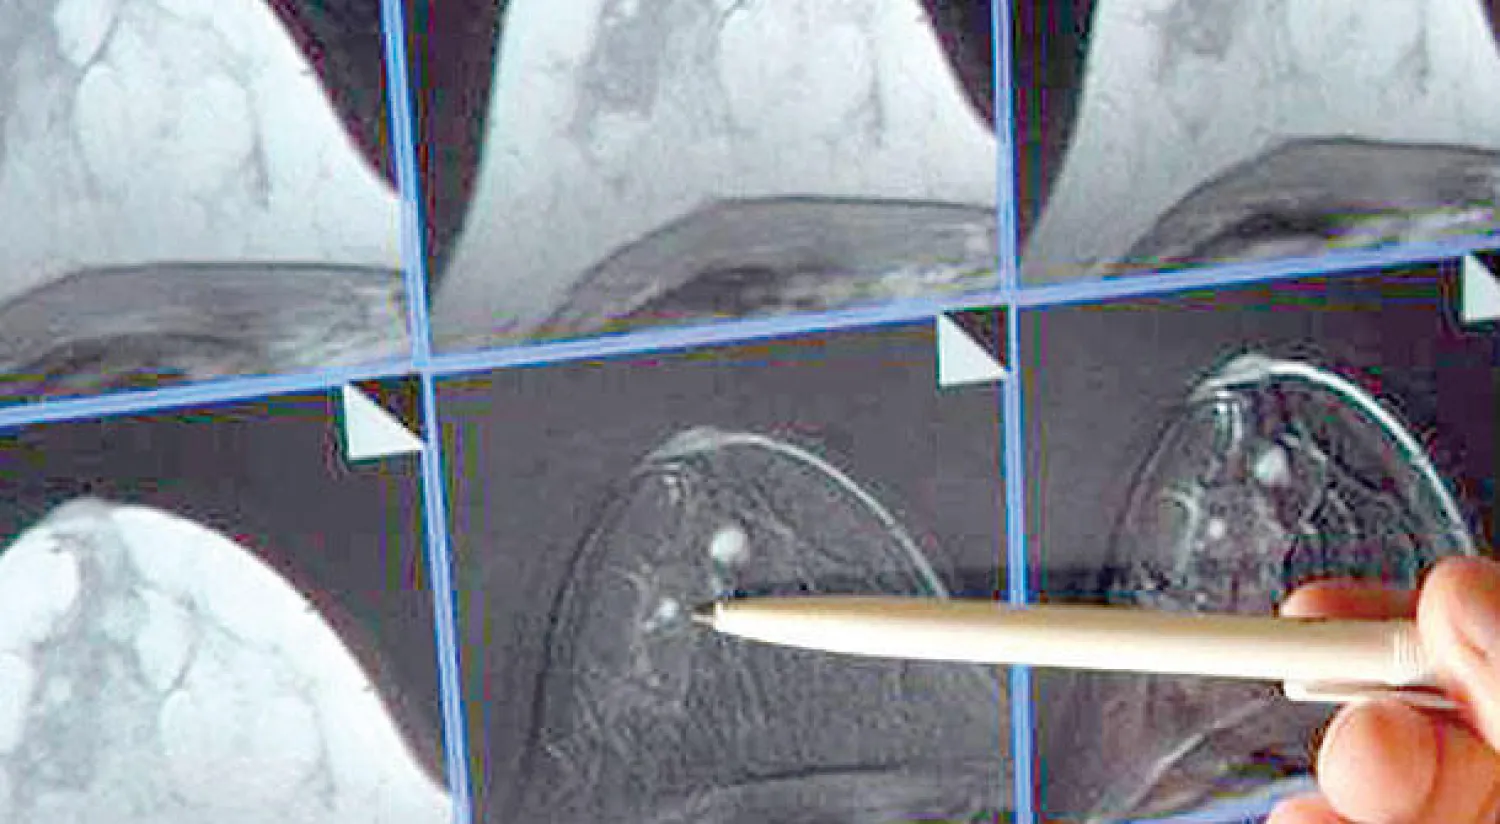

نسبة الخطأ في التشخيص انخفضت في ألمانيا إلى 5 في المائة (د.ب.أ)